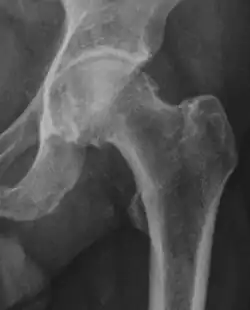

Projectional radiography ("X-ray") is often considered first line for FAI.[10] Anterior-posterior pelvis and a lateral image of the hip in question should be attained.[10] A 45-degree Dunn view is also recommended.[10][19]

| Femoral head-neck offset | ![]() |

Offset of the femoral head with regard to most prominent aspect of the femora neck | >10 mm |